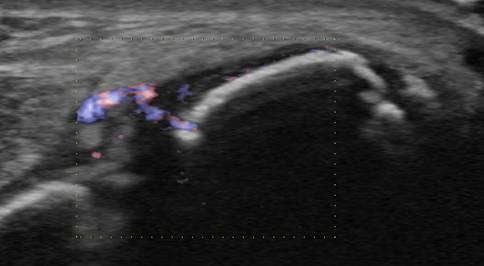

Tụ mủ dưới màng xương

Viêm xương tủy

» Thông tin: Nam giới – 11 tuổi.

» Lâm sàng: Sưng đau cẳng chân.

# Tụ mủ dưới màng xương.